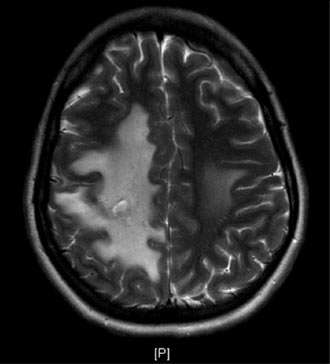

The blockage can result in brain swelling (edema), stroke, and/or bleeding in the brain (Figure 2).

Brain imaging studies such as MRI and CT are commonly used to demonstrate the clot in the cerebral venous sinuses. If necessary, catheter angiography is also performed to visualize the relatively small clots or when catheter based clot-removing treatment is needed (Figure 1).